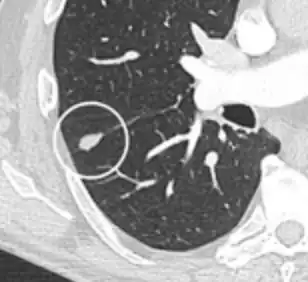

• Bubble-like lucencies in the nodule indicate cancer:[9]